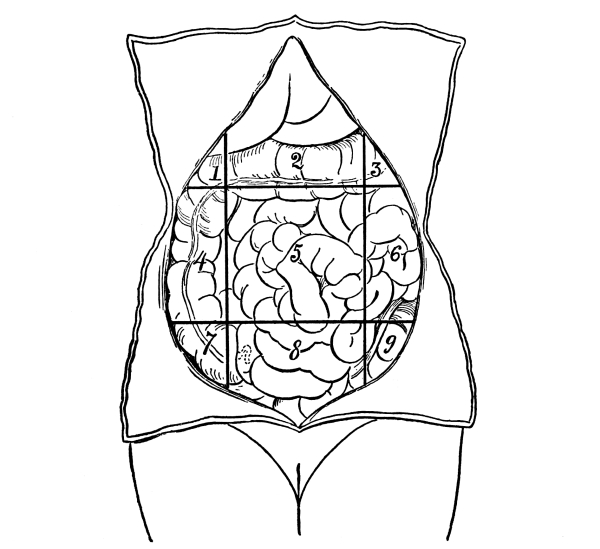

| The Abdomen and the Organs of Digestion and Excretion | 132 |

The Abdominal Cavity, 132—Muscles of the Abdomen, 132—The Peritoneum, 134—Abdominal Regions, 134—Salivary Digestion, 136—The Pharynx, 139—The Esophagus, 138—The Stomach, 138—Gastric Digestion, 139—Vomiting, 140—Intestinal Canal, 141—The Small Intestine, 142—Intestinal Digestion, 143—Absorption in Intestine, 144—The Large Intestine, 145—Food and Metabolism, 147—The Liver, 149—The Gall-bladder, 152—The Pancreas, 153—The Spleen, 153—The Suprarenal Capsules, 154—The Kidneys, 155—The Urine, 156—The Ureters, 159—The Bladder and Urethra, 159. |